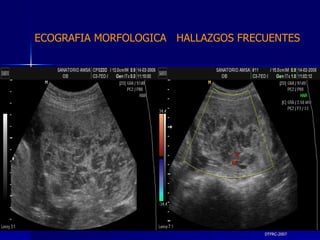

DTFRC-2007 ECOGRAFIA MORFOLOGICA  HALLAZGOS FRECUENTES   MATERIAL Y METODO ES UN ESTUDIO DESCRIPTIVO, RETROSPECTIVO  DE ESTUDIO ECOGRA FICOS REALIZADOS ENTRE MARZO 07 A MARZO 08 EQUIPO DE ALTA RESOLUCION   VOLUSON 730 PRO  MEDISON SA 8000 live MEDISON SA 8000SE CRITERIO DE INCLUSION:   POBLACION GENERAL    GESTACIONES  20 a 24 SEMANAS   UNIVERSO  N 211

DTFRC-2007 ECOGRAFIA MORFOLOGICA  HALLAZGOS FRECUENTES   GENITOURINARIA DISPLASIA RENAL MULTIQUISTICA  3 HIDRONEFROSIS  2 QUISTE DE OVARIO FETAL  1 SISTEMA DIGESTIVO DILATACION INTESTINAL  2  SISTEMA ESQUELETICO   PIE BOT  2  20 % 6 % 6 %

DTFRC-2007 ECOGRAFIA MORFOLOGICA  HALLAZGOS FRECUENTES   OTROS HIGROMA QUISTICO  2 ENFERMEDAD ADENOMATOSA PULMONAR  1 ARTERIA UMBILICAL UNICA  2 HIDROPS FETAL NO INMUNE  1 QUISTE DE CORDON UMBILICAL  1 ALTERACION DE LIQUIDO ANMIOTICO  2 SINDROME TRAFUSIONAL FETO FETAL 1 LABIO LEPORINO  2 TOTAL  12  42 %